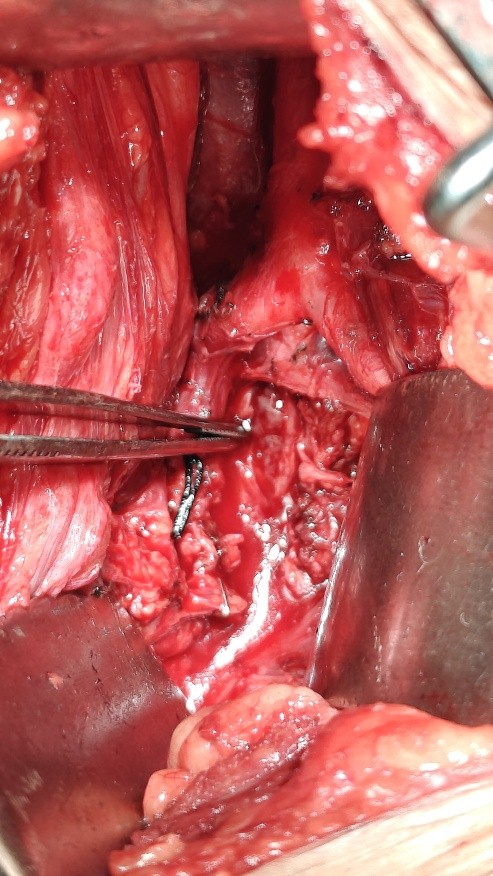

Under general anesthesia, the pararectus approach was used to explore the tumor. After dissecting the common, internal, and external iliac arteries and vein, tumor was identified near the sciatic foramen (Fig. 4); however, proximally, the tumor was right behind the common iliac vein, which looked flattened and thrombosed. The sciatic nerve sheath was incised longitudinally along the length, which exposed the tumor tissue. The tumor was grayish in color and fragmented nerve fibers were coming out along with the tumor tissue. Intraoperative morphology was different from the pre-operative diagnosis of schwannoma or neurofibroma. There was no delineation between tumor and nerves; to avoid further neurological damage, only decompression was performed.

Figure 4: Showing sciatic nerve, behind the bifurcation of common iliac artery, through pararectus approach.

The patient was turned laterally, and tumor was exposed posteriorly from the Kocher-Langenbeck approach of the hip. The nerve, as shown in the figure, was thickened and firm. The nerve sheath was incised, but no tumor delineation was possible (Fig. 5). A small finger-like extension coming out from the sciatic nerve was present over the surface of about 1.5 cm, which was excised (glomangiomatosis) and sent for histopathological examination. A biopsy was also taken after decompression of the nerve and the wound was closed.

Figure 5: Showing the sciatic nerve through the Kocher-Langenback approach, the first image shows the sciatic nerve after dissection, and the second after longitudinal incision over the nerve.